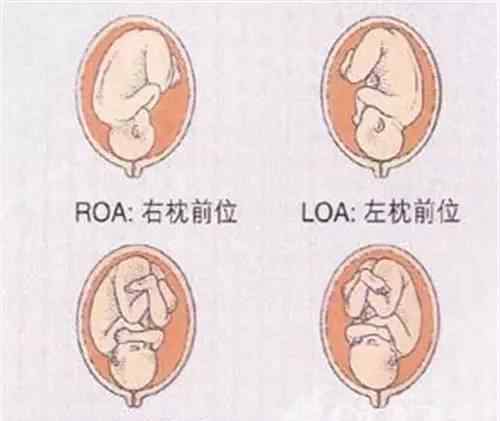

◆胎位loa是什么意思?

b超检查,其中报告有胎位loa,是什么意思?很多妈妈都不太了解。作为一个孕妇,有一半的专家告诉你,LOA指的是左枕前位。也就是说可以自然交付。这个问题我们再详细说说。

意思是骨头在骨盆的前面、后面或对面。比如枕骨在骨盆左侧,面向前方,胎位就是左枕前(LOA),这是最常见的胎位。

◆胎位roa和loa的区别:

一般来说,胎位roa是右枕,胎位loa是左枕。右枕前指胎儿枕骨在右侧前方,左枕前指胎儿枕骨在左侧前方。

胎位roa是正常胎位,孕妇不用紧张。Roa露在上方,枕骨在骨盆右侧,面向前方,胎位为右侧枕前位。自然分娩的最佳胎位,这个胎位排第二。产道无异常,自然分娩即可。

胎位loa也是正常胎位,指的是左枕前位,意思是枕骨在骨盆左侧,面向前方,所以胎位是左枕前位,是最常见的正常胎位,也是比较容易的胎位。

胎位指示点与母体骨盆的关系称为胎儿方位,而枕位以枕骨为指示点,根据指示点与母体骨盆的关系有不同的胎位。Loa是指胎儿的枕骨位于母亲骨盆的左前方,是最常见的胎位,可以自然分娩。所以根据以上可以看出,左侧枕前(loa)是最常见的胎位,也是自然分娩的最佳胎位,枕骨在骨盆左侧,面向前方。

Roa和loa都是正常胎位,孕妇不用担心。